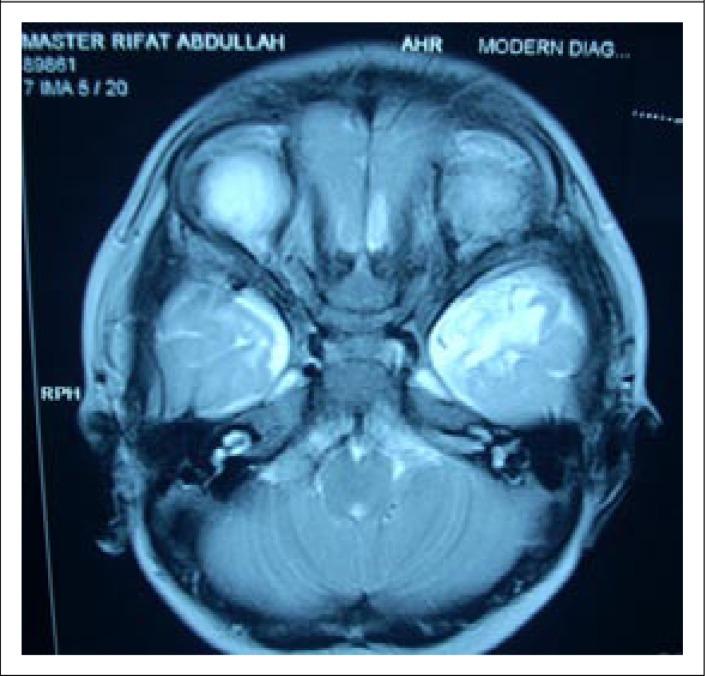

A boy aged 4 months 7 days was admitted to the Intensive Care Unit (ICU) of the Dhaka Hospital of icddr,b, Dhaka, Bangladesh, with the problems of acute watery diarrhoea with some dehydration, pneumonia, lethargy, and hypernatraemia (serum sodium of 201 mmol/L). Correction for hypernatraemia was tried by using only oral rehydration salt (ORS) solution. Seizures occurred during correction of the hypernatraemia. These were difficult to control and required three doses of injection lorazepam, a loading dose of injection phenobarbitone, followed by injection phenytoin and finally two doses of injection mannitol (even though there was no clinical or imaging evidence by ultrasonography or computed tomography of cerebral oedema). The correction was continued with ORS, and all the anticonvulsants were successfully weaned without any further seizures, and the patient recovered without any overt neurological sequelae. We present a case report of extreme hypernatraemia, which was successfully managed using only ORS.

一名4个月7天大的男童因急性水样腹泻伴轻度脱水、肺炎、嗜睡和高钠血症(血清钠201 mmol/L)入住孟加拉国达卡icddr,b达卡医院重症监护病房(ICU)。仅使用口服补液盐(ORS)溶液尝试纠正高钠血症。在纠正高钠血症过程中发生了惊厥。惊厥难以控制,需要注射三剂劳拉西泮、一剂负荷量苯巴比妥注射液,随后注射苯妥英,最后注射两剂甘露醇(尽管超声或计算机断层扫描均无脑水肿的临床或影像学证据)。继续用ORS进行纠正,所有抗惊厥药物均成功撤停,未再发生惊厥,患者康复,无明显神经后遗症。我们报告一例极重度高钠血症病例,仅用ORS成功治疗。